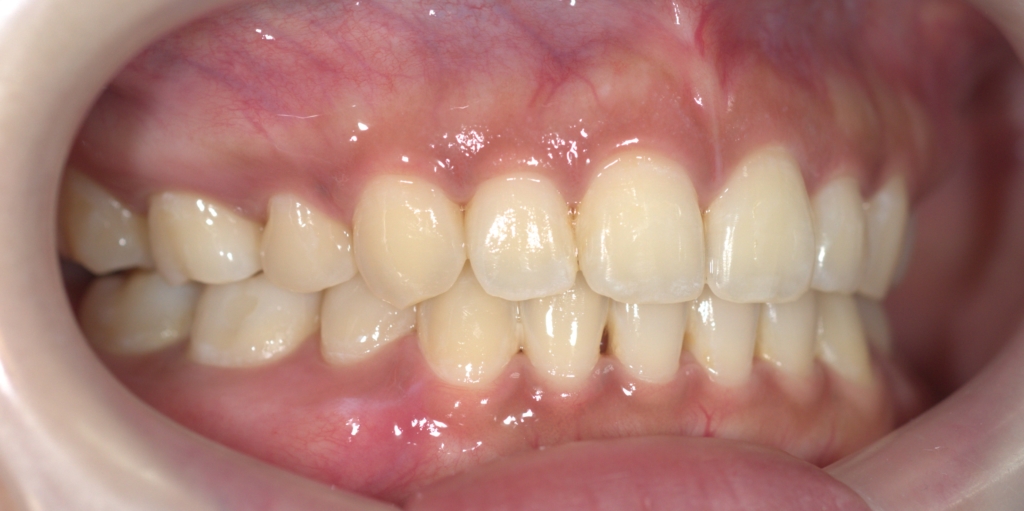

【After】

矯正後の状態をレントゲン写真で確認すると、

【保定】 上下ともフィックスタイプ&クリアリテーナー

【治療期間】 約2年間

【治療費用】 83万8千円

【治療装置】 スタンダードtypeのマルチブラケットシステム、

アンカースクリューを2本

PLAS & パラタルバー